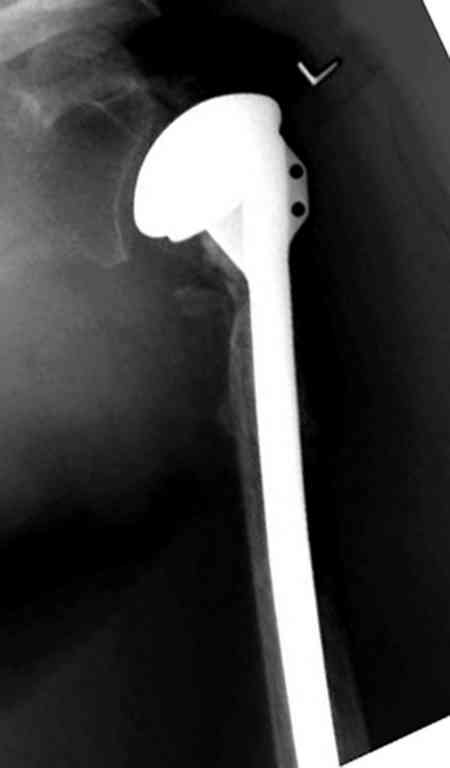

Неправильно выбранная тактика по фиксации или технические ошибки во время операции могут привести к серьезным осложнениям. Здесь привожу

пример из нашей практики, вроде обычный перелом шейки, фиксированный популярным методом "Сиэтла" - множественными спицами 2.8 мм с резьбой на конце.

При первичном осмотре в поликлинике через 3 недели обнаружили миграцию двух спиц, срочно госпитализированному на второй день перед операцией на всякий случай сделали снимок, одна спица находилась под ключицей в шейном отделе (на снимке).